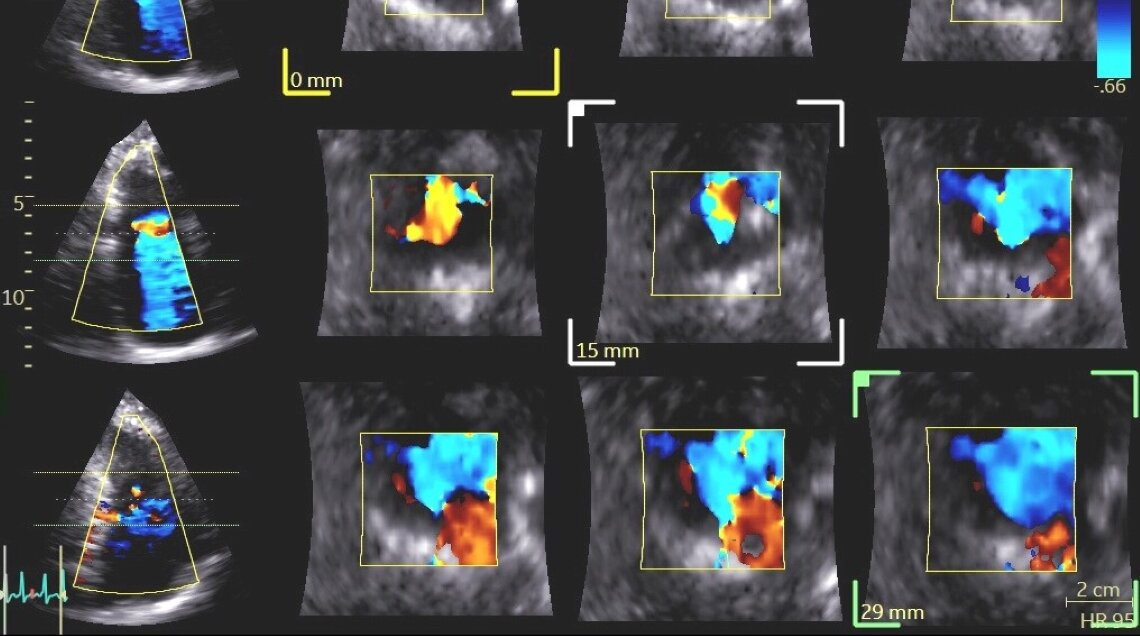

- Ecocardiogramma color-Doppler: esame di riferimento per valutare la gravità del rigurgito, la causa e l’impatto su ventricolo e atrio destro.